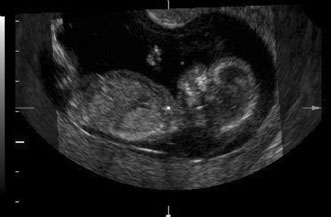

Maternal serum screening can identify pregnant women who are at an increased risk for having a baby with certain birth defects. Patient-specific risks for open spina bifida, Down syndrome and trisomy 18 (Edwards syndrome) (Fig. 1) can be determined by measuring the levels of certain proteins in maternal serum and combining those data with the patient's maternal age and clinical information.10 Women with a positive screen should be offered a definitive diagnostic test.

Fig. 1. Three-dimensional ultrasound showing typical pattern of trisomy 18. A clenched fist with the index finger overlapping the third and fourth fingers is distinctive of this disorder. Image courtesy of GE Medical Systems.